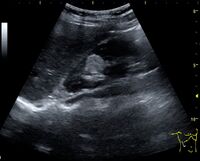

Figure 3. Measures of the kidney. L = length. P = parenchymal thickness. C = cortical thickness.[1]

Cortical thickness should be estimated from the base of the pyramid and is generally 7–10 mm. If the pyramids are difficult to differentiate, the parenchymal thickness can be measured instead and should be 15–20 mm (Figure 3). The echogenicity of the cortex decreases with age and is less echogenic than or equal to the liver and spleen at the same depth in individuals older than six months. In neonates and children up to six months of age, the cortex is more echogenic than the liver and spleen when compared at the same depth.[1]